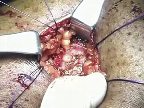

Once the four additional sutures have been placed, large, blunt right-angles are placed at the mid-aspect of the ileum protruding above the skin and used as a fulcrum to facilitate intussusception of the rosebud stoma. Multiple right-angles can be utilized at this point of the procedure to help facilitate circumferential intussusception of the stoma, Figure 3.

After intussusception is completed, the four previously placed sutures are tied down to secure the rosebud stoma in position. Two or three interrupted 4-0 chromic sutures are placed between the 2-0 Vicryl sutures. A catheter is not placed as in our experience the single J ureteral stents are sufficient to ensure renal and conduit drainage, Figure 4. With the rosebud stoma completed, a pelvic drain is placed and the operation completed.